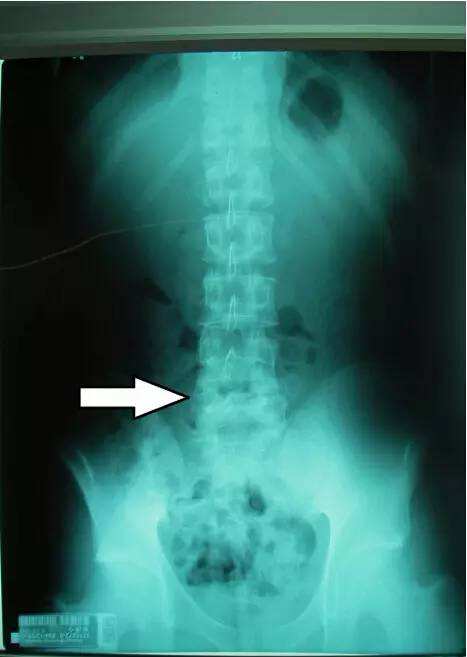

此病常常侵犯年轻男性。“医生误诊是由于此病初发时还未出现关节 ...